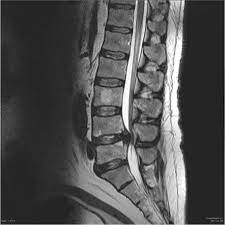

A few years ago, I had a cyst that formed on my lower spine that caused extreme pain. I had injured it working but continued to work—with a cane in one hand to hold me steady. At one point I went to the emergency room as the pain became intense as nerves paralyzed my left side down to my toes. The emergency doctors filled me a syringe of pain killer so x-rays of my back could be taken. The tests proved my pain’s source but they could only offer more drugs to “manage my pain”, a phrase I would learn to hate hearing.

Today, years later, I still do these exercises to maintain a healthy spine. God caught my attention and guided me to help. Oh, and the specialist? I finally saw him four months later. He took x-rays, of course, and compared them to the x-rays the ER took months earlier. “I don’t know what you’re doing but keep doing it! You’re healing well!”, he said. My response to him was, “Praise God! When everyone else wanted to merely manage pain, He answered my prayer to be healed.”